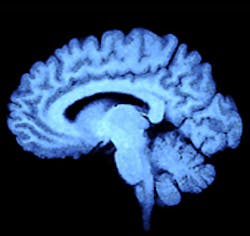

UK researchers have shown that infrared and Raman spectroscopy - coupled with statistical analysis - can be used to differentiate between normal brain tissue and different tumor types.

Currently, when surgeons are operating to remove a brain tumor it can be difficult to spot where the tumor ends and normal tissue begins. But the team of researchers led by Professor Francis Martin at Lancaster University (Lancaster, UK) has shown it is possible to spot the difference between diseased and normal tissue using Raman spectroscopy, giving accurate results in seconds.

The development means it is now theoretically possible to test living tissue during surgery, helping doctors to remove the complete tumor whilst preserving intact adjacent healthy tissue.